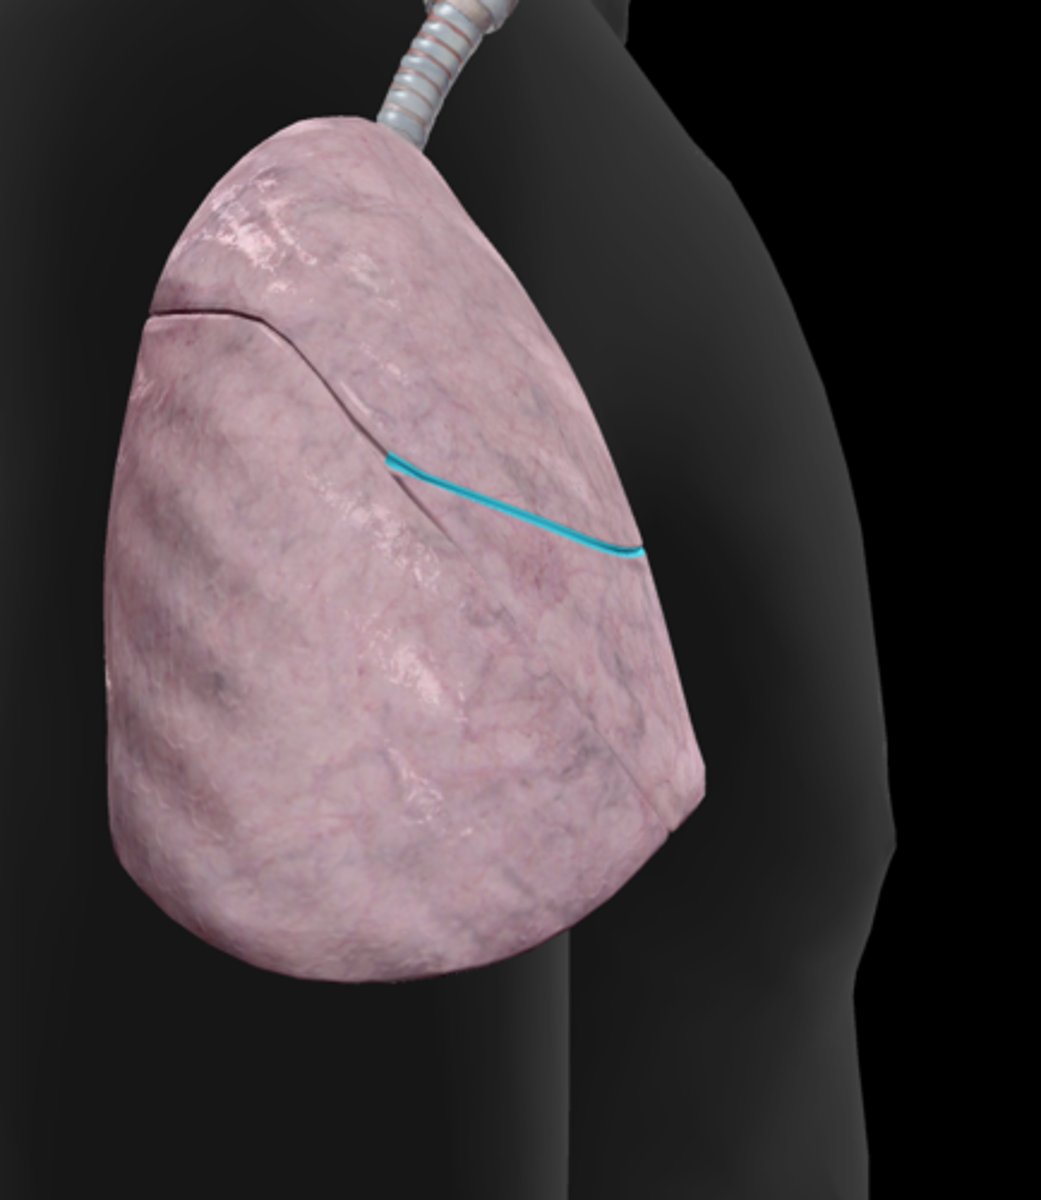

Horizontal fissure

Oblique fissure